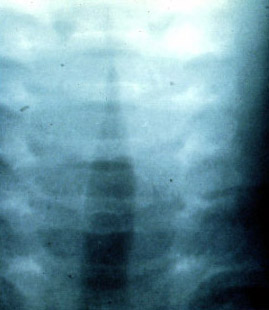

AP projection of a child with viral laryngotracheobronchitis (croup) showing the characteristic narrowing at the subglottic level (steeple sign).